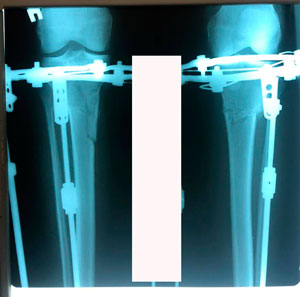

Исходник - 40 лет

Диагноз: варусная деформация голеней + Ротация с обеих сторон.

Дата операции - 09.07.2020

на фиксации